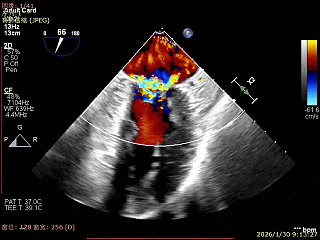

主动脉瓣大量反流

经胸超声报告提示:患者二尖瓣2区及3区前叶关闭时脱入左房,二尖瓣重度反流(MR 4+),患者LA前后径约52mm,LVEDD约68mm,LVESD约42mm,EF值:65%,经胸超声测二尖瓣瓣口面积约6.1cm2,主动脉瓣无冠瓣脱垂并中重度反流,三尖瓣中度反流,估测中度肺动脉高压。

Bicomm切面看2区脱垂

上Color,可见反流主要来自于3区